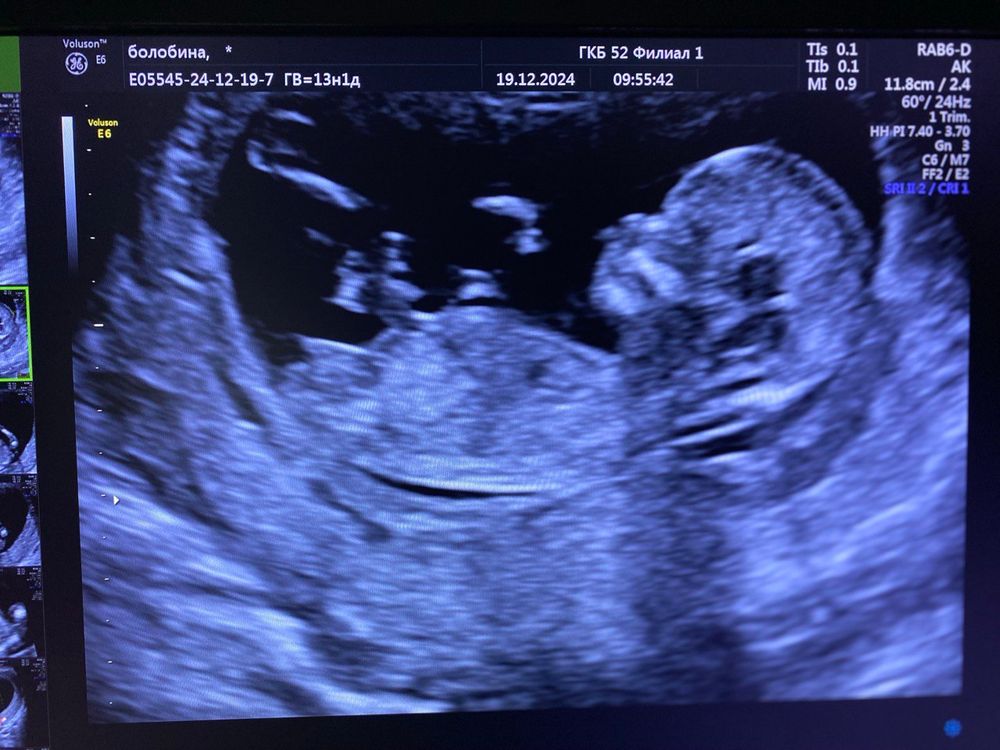

Кто же ты 🥰

Девочка) Половой бугорок горизонтальный )

SladkayaVi, хотелось бы, все бабушки увидели парня, а врач вообще промолчала, сказала рано ещё смотреть)

SladkayaVi, как узнаю - отпишусь))) Я врачу сказала что есть 2 мальчика, тоже думаю что она побоялась обнадежить. Мне со вторым тоже уверенно сразу сказали, но у мальчиков бугорок нагляднее)

SladkayaVi, сегодня были на узи - это девочка 🩷

Такая симпатичная фотка с узи, пусть будет девочка)🌸